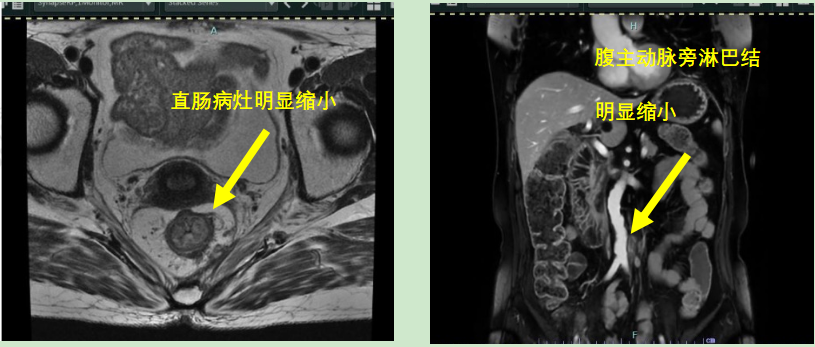

本次參賽病例為一例直腸神經(jīng)內(nèi)分泌癌伴肝轉(zhuǎn)移病灶的老年女性患者,影像科專家評(píng)估分期T3cN1M1,外科專家評(píng)估患者暫無(wú)手術(shù)指征,經(jīng)與腫瘤內(nèi)科專家和放療科專家行MDT會(huì)診后,予患者先行化療?;颊呋驒z測(cè)外送結(jié)果提示患者敏感性較高的化療藥物為:伊立替康和卡培他濱?;颊咝幸晾婵?FU+亞葉酸鈣+貝伐單抗治療4周期后,病情評(píng)估為穩(wěn)定,后患者至放療科行卡培他濱化療聯(lián)合直腸原發(fā)灶局部放療,直腸原發(fā)灶獲得影像學(xué)部分緩解。后患者出現(xiàn)腹主動(dòng)脈旁新發(fā)腫大淋巴結(jié)。再次行病理科、影像科、腫瘤內(nèi)科和放療科多學(xué)科協(xié)作診療,考慮患者為神經(jīng)內(nèi)分泌癌,根據(jù)2023歐洲神經(jīng)內(nèi)分泌腫瘤學(xué)會(huì)推薦轉(zhuǎn)移性消化系統(tǒng)NEC治療以順鉑聯(lián)合依托泊苷為主。并且神經(jīng)內(nèi)分泌癌2024 CSCO指南推薦對(duì)于既往接受過(guò)系統(tǒng)治療且持續(xù)進(jìn)展、缺乏標(biāo)準(zhǔn)治療的轉(zhuǎn)移性NEC患者,也可考慮免疫治療。因此,予患者行依托泊苷聯(lián)合順鉑治療,并且聯(lián)合索凡替尼和恩沃利單抗。兩周期用藥后復(fù)查示腹主動(dòng)脈旁新發(fā)腫大淋巴結(jié)較前明顯縮小,其余病灶穩(wěn)定。 初治時(shí) 直腸病灶放療后出現(xiàn)新發(fā)腹主動(dòng)脈淋巴結(jié) 治療后肝臟病灶穩(wěn)定,直腸原發(fā)灶和腹主動(dòng)脈腫大淋巴結(jié)明顯縮小 王明 主任醫(yī)師 乳腺與腹部腫瘤放療科(放療一科)主任 專業(yè)擅長(zhǎng):各種胸部腫瘤:如乳腺癌、食管癌的放化療、免疫、靶向治療,以及各種腹部腫瘤的放化療,尤其擅長(zhǎng)各種消化道腫瘤:胃癌、肝癌、膽管癌、胰腺癌、結(jié)直腸癌的放療、化療、靶向等綜合治療。泌尿系腫瘤:腎癌、膀胱癌、前列腺癌等腫瘤的綜合治療。 張一擎 主治醫(yī)師 滄州市中心醫(yī)院乳腺與腹部腫瘤放療科(放療一科) 苗玉 副主任醫(yī)師 滄州市中心醫(yī)院病理科 專業(yè)擅長(zhǎng):消化系統(tǒng)腫瘤及消化道早癌篩查病理診斷。 孫敏 副主任醫(yī)師 磁共振成像科 從事臨床工作十多年,對(duì)臨床常見(jiàn)疾病的核磁診斷有豐富的經(jīng)驗(yàn)。 李哲 副主任醫(yī)師 滄州市中心醫(yī)院腫瘤內(nèi)一科 楊立勝 主治醫(yī)師 滄州市中心醫(yī)院結(jié)直腸肛門外科 專業(yè)擅長(zhǎng):結(jié)直腸癌、肛周常見(jiàn)疾病、盆底疾病的外科診療。